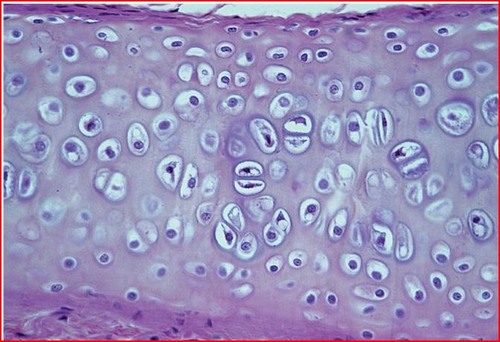

cartilage

rigid, providing protections, frameworks attachments and support